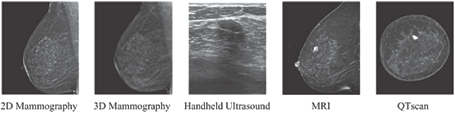

QT Breast Scanner is a fixed, mechanical scanner used to evaluate the breast without the use of either ionizing radiation or compression associated with mammography, or the contrast dyes (as environmentally impactful gadolinium etc.) injections required for breast magnetic resonance imaging (MRI). With the QT Breast Scanner, the patient lies comfortably on a table which contains an opening through which the breast is placed in a warm water bath (see Image 1) and gently immobilized using a magnetic retention pad fixed to a magnetic rod. The QT Breast Scanner differs from the handheld ultrasound used in breast imaging in that it utilizes reflection and transmission data from low-frequency sound waves, providing a significant increase in diagnostic information using the speed of sound characteristics of the breast and acquiring in true 3D a very accurate rendering of the breast tissue. The QT Breast Scanner provides sub-millimeter, high-definition, image resolution enabling identification of normal and abnormal breast structures and the accurate depiction of the precise shape and location of findings. The technology uniquely quantifies breast density using ratio of breast fibroglandular tissue volume (FGV) to total breast volume (TBV) transmission and reflection images’ information of patient’s breast to further personalize a patient’s management recommendations. Surface-to-volume ratios and volumetric doubling time growth rate characteristics can be calculated to determine significance of lesions and improve specificity of the ultrasound.